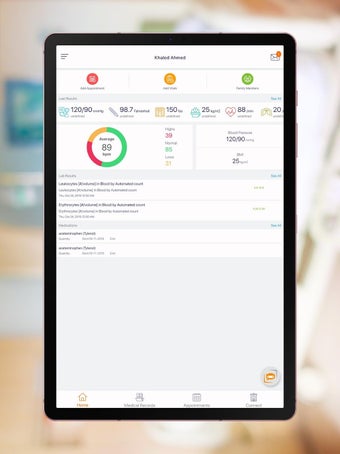

Carepassport là một ứng dụng Android cung cấp cho bệnh nhân một giải pháp toàn diện để quản lý dữ liệu y tế của họ. Ứng dụng cho phép bệnh nhân truy cập và lưu trữ an toàn dữ liệu y tế của mình, lên lịch hẹn, xem hình ảnh y tế, báo cáo xét nghiệm và lâm sàng từ các nhà cung cấp khác nhau, và chia sẻ chúng bằng công nghệ tính toán di động tiên tiến. Với Carepassport, bệnh nhân có thể dễ dàng quản lý nhu cầu chăm sóc sức khỏe của mình chỉ với vài lần chạm trên thiết bị di động của họ.

Một trong những tính năng quan trọng nhất của ứng dụng là việc truy cập dữ liệu y tế một chạm dễ dàng. Bệnh nhân có thể truy cập dữ liệu y tế của mình hoặc dữ liệu đại diện gia đình một cách an toàn và nhanh chóng, làm cho nó trở thành một công cụ tuyệt vời để quản lý lịch sử bệnh án của họ. Ứng dụng cũng cho phép người dùng tìm kiếm các phòng khám và bệnh viện gần đó, lên lịch hẹn, và thậm chí nhận chỉ đường đến cuộc hẹn của họ qua Uber. Ngoài ra, bệnh nhân có thể giao tiếp với nhà cung cấp chăm sóc của họ qua tin nhắn an toàn, chia sẻ hình ảnh y tế và cho phép thành viên gia đình truy cập dữ liệu y tế của họ thông qua cài đặt proxy an toàn. Cuối cùng, ứng dụng cung cấp tài liệu giáo dục liên quan đến chăm sóc sức khỏe và có thể kết nối với các thiết bị đeo được hoặc nhập dữ liệu y tế thủ công.

Nhìn chung, Carepassport là một ứng dụng hữu ích cho bất kỳ ai muốn có quyền truy cập an toàn và tiện lợi vào dữ liệu y tế của mình. Giao diện thân thiện với người dùng, công nghệ tính toán di động tiên tiến và tính năng tuyệt vời của ứng dụng làm cho nó trở thành một ứng dụng cần thiết cho bất kỳ ai muốn quản lý sức khỏe của mình tốt hơn.